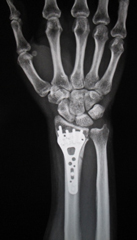

1. 橈骨遠位端骨折

粉砕の強い場合、関節内に骨折が及ぶ場合は手術を行います。プレートを用いた整復固定を行いますが、粉砕の強い場合は創外固定や人工骨充填を併用します。